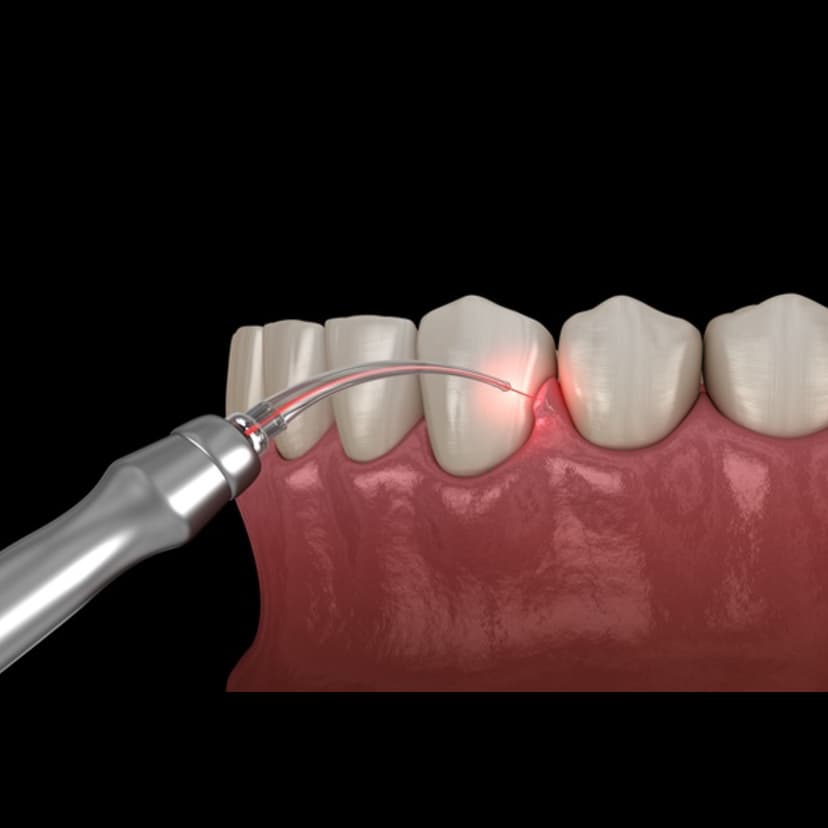

Treatment for gum disease and recession

Key Features: